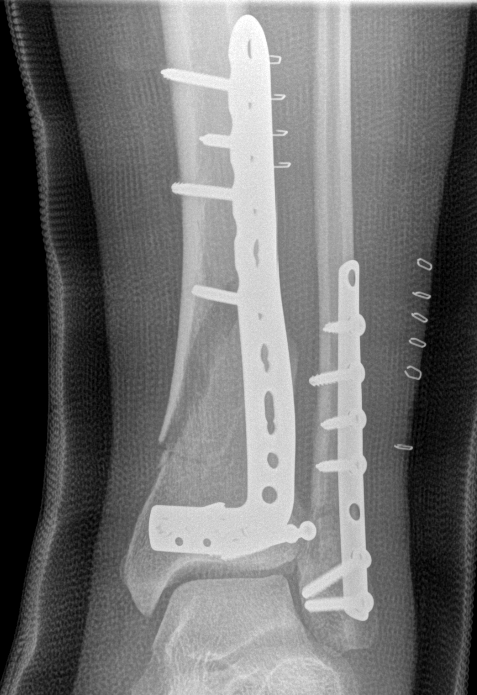

B. Distal Tibial ORIF with plate

Indications

- too distal to nail

- very comminuted / unstable

- intra-articular extension

Technique

1. Consider fixing the fibula

- will aid reduction / avoid malunion

- help control very unstable fractures

2. Anatomically contoured plates

- options of medial plate v anterolateral plate

- medial plate for varus deformity

- anterolateral plate for valgus deformity